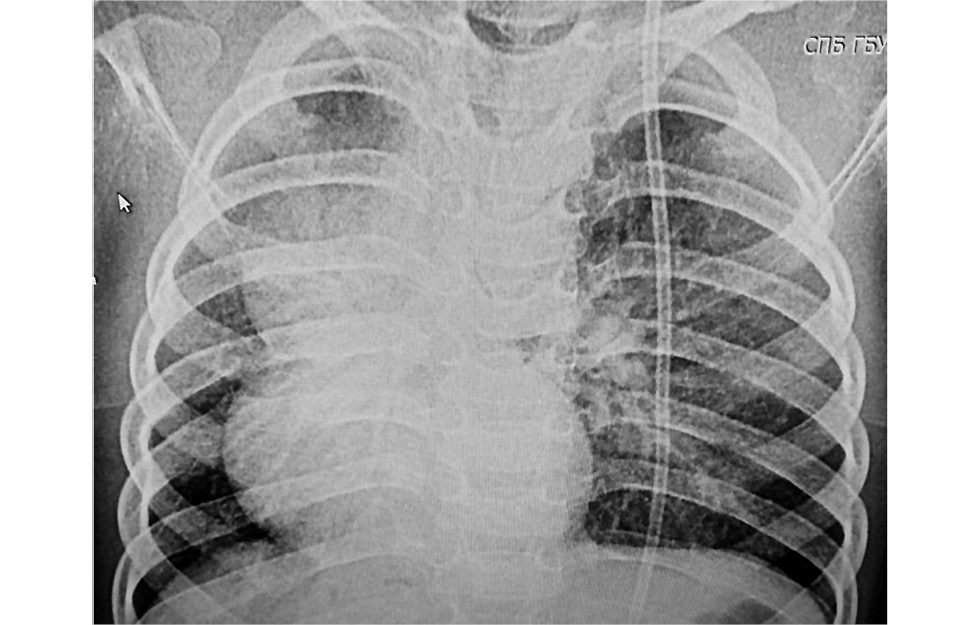

Послеоперационный период протекал без осложнений. Больная экстубирована на 2 сут после операции, плевральные дренажи удалены на 7 сут. Трижды проводились санационные БС. В динамике отмечено улучшение пневматизации правого лёгкого (рис. 8).

Рис. 8. Рентгенограмма органов грудной полости на 21 сут после операции.

Fig. 8. Chest X-ray on day 21 after surgery.

Девочка выписана через 28 дней после операции в удовлетворительном состоянии без признаков ДН. Однако справа по задней поверхности грудной клетки сохранялось ослабленное дыхание (частота дыхательных движений до 50 в мин), а также асимметрия грудной клетки и смещение органов средостения вправо.